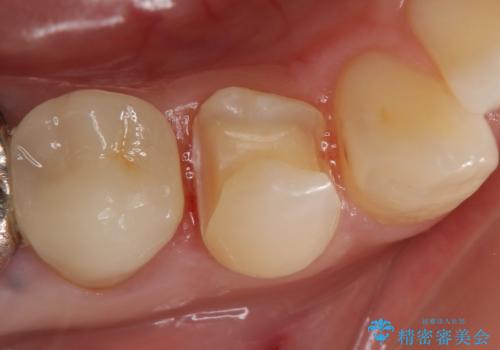

- 甘いものを食べると右下4番目の歯がしみるので診て欲しいといらっしゃった方の症例です。

古い銀歯と虫歯を除去後、PGA(ゴールド)インレーによる修復を行いました。